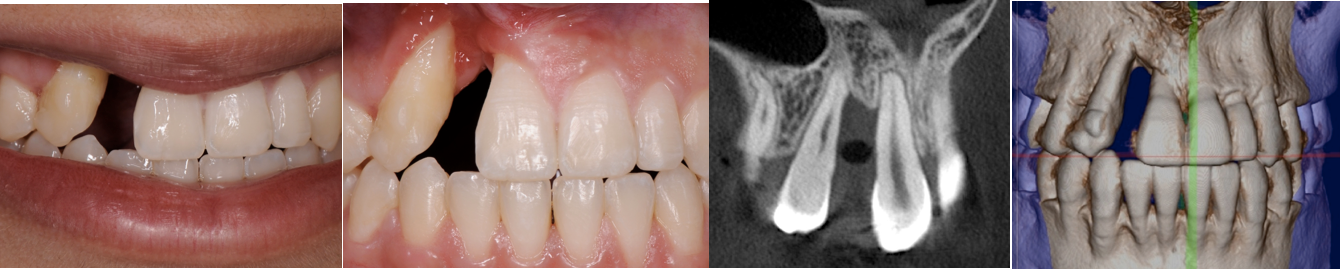

The patient had a congenitally missing upper right lateral incisor. Orthodontic treatment was performed to create the necessary space for a dental implant. Unfortunately, the implant failed, and so did several subsequent attempts to bone graft. These failures resulted in a visible smile deformity, that got worse after each failed procedure.

After the 3rd bone graft failed, the patient sought second opinions. She was a college sophomore at the time. Using a combination of interdisciplinary therapies, including S.M.A.R.T. minimally invasive bone grafting, Dr. Ernesto Lee was able to tridimensionally reconstruct this severe defect and place implants to restore the patient’s smile. The S.M.A.R.T. bone graft was also extended to treat adjacent teeth with thin/dehisced bone.

A long-term CAD/CAM fabricated temporary restoration is in place while she finishes medical school at an out-of-state university. The treatment of this case was published in detail in a special issue of the Compendium of Continuing Education in Dentistry, one of the largest circulation journals in our profession.